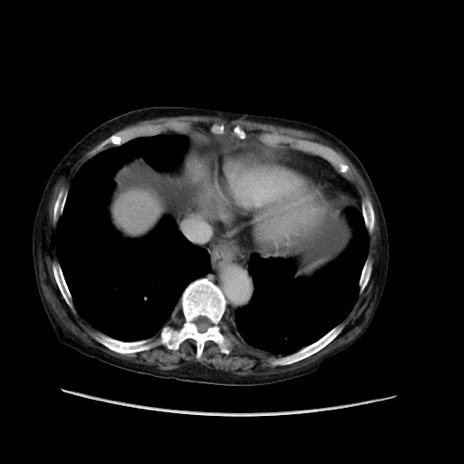

冠状断像

【症例】80歳代 女性

【主訴】腹部膨満感

【現病歴】他院にて肝硬変にてフォロー中。1週間前から便秘、腹部膨満感、臍部腫瘤あり受診となる。

【既往歴】肝硬変

【身体所見】腹部膨隆あり、皮膚変化なし、疼痛なし。

【データ】WBC 4600、CRP 0.25